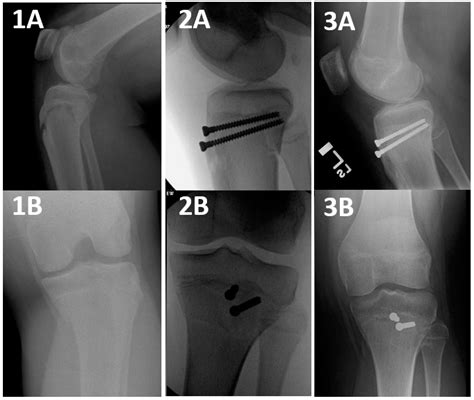

Orthopedic surgeons often categorize these injuries based on the Ogden classification system, which helps guide treatment decisions. This classification ranges from simple, non-displaced fractures to complex injuries that extend into the knee joint.

Type Severity Description Typical Treatment

Type I Small fracture at the distal part of the tuberosity. Conservative (casting)

Type II Fracture extends through the secondary ossification center. Surgery often required

Type III Fracture extends into the articular surface of the knee. Surgical intervention

However, if the fragment is displaced or if the knee joint is compromised, surgical intervention is mandatory. The surgical procedure typically involves:

• Open Reduction Internal Fixation (ORIF): The surgeon makes an incision to visualize the bone fragment.

• Hardware Placement: The loose piece of bone is secured back to the main tibia using screws, wires, or specialized anchors.

• Tendon Repair: If the patellar tendon is damaged during the avulsion, it is repaired and reinforced during the procedure.